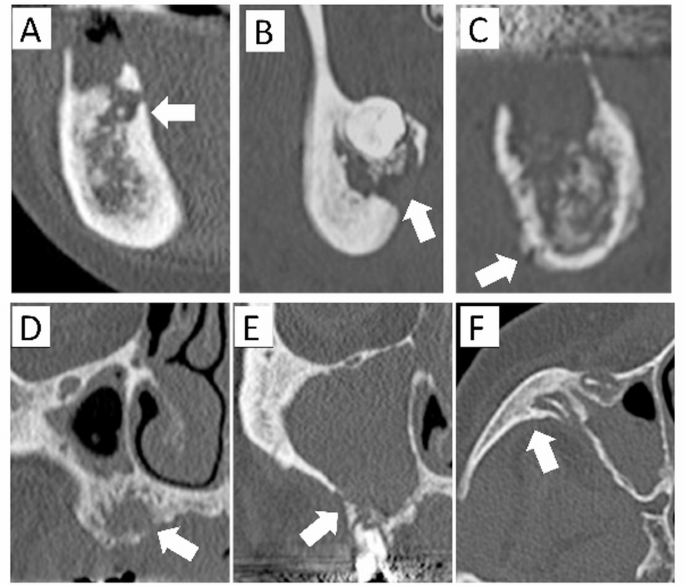

Osteolysis (Fig. 1).

Classified based on the extent of bone resorption in the maxilla and mandible:

(−): No osteolysis.

Localized type

Bone marrow or cortical osteolysis does not extend:

-

(1)

To the wall of the maxillary sinus, or

(2)

To the level of the superior border of the mandibular canal.

Extended type

Bone marrow or cortical osteolysis extends:

Advanced type

Beyond the maxillary bone, involving the adjacent zygomatic bone, or

Beyond the level of the inferior border of the mandibular canal.

Note: In the anterior mandible, the reference point is the line connecting the mental foramina.

Classification of mandibular osteolysis (A–C) and maxillary osteolysis (D–F).(A) Localized type, not extending to the mandibular canal (arrow). (B) Extendedtype, reaching the mandibular canal (arrow). (C) Advanced type, extending to thelower portion of the mandibular canal (arrow). (D) Localized type, not extending tothe floor of the maxillary sinus (arrow). (E) Extended type, reaching the floor of themaxillary sinus (arrow). (F) Advanced type, extending beyond the maxillary bone,such as to the zygomatic bone (arrow).